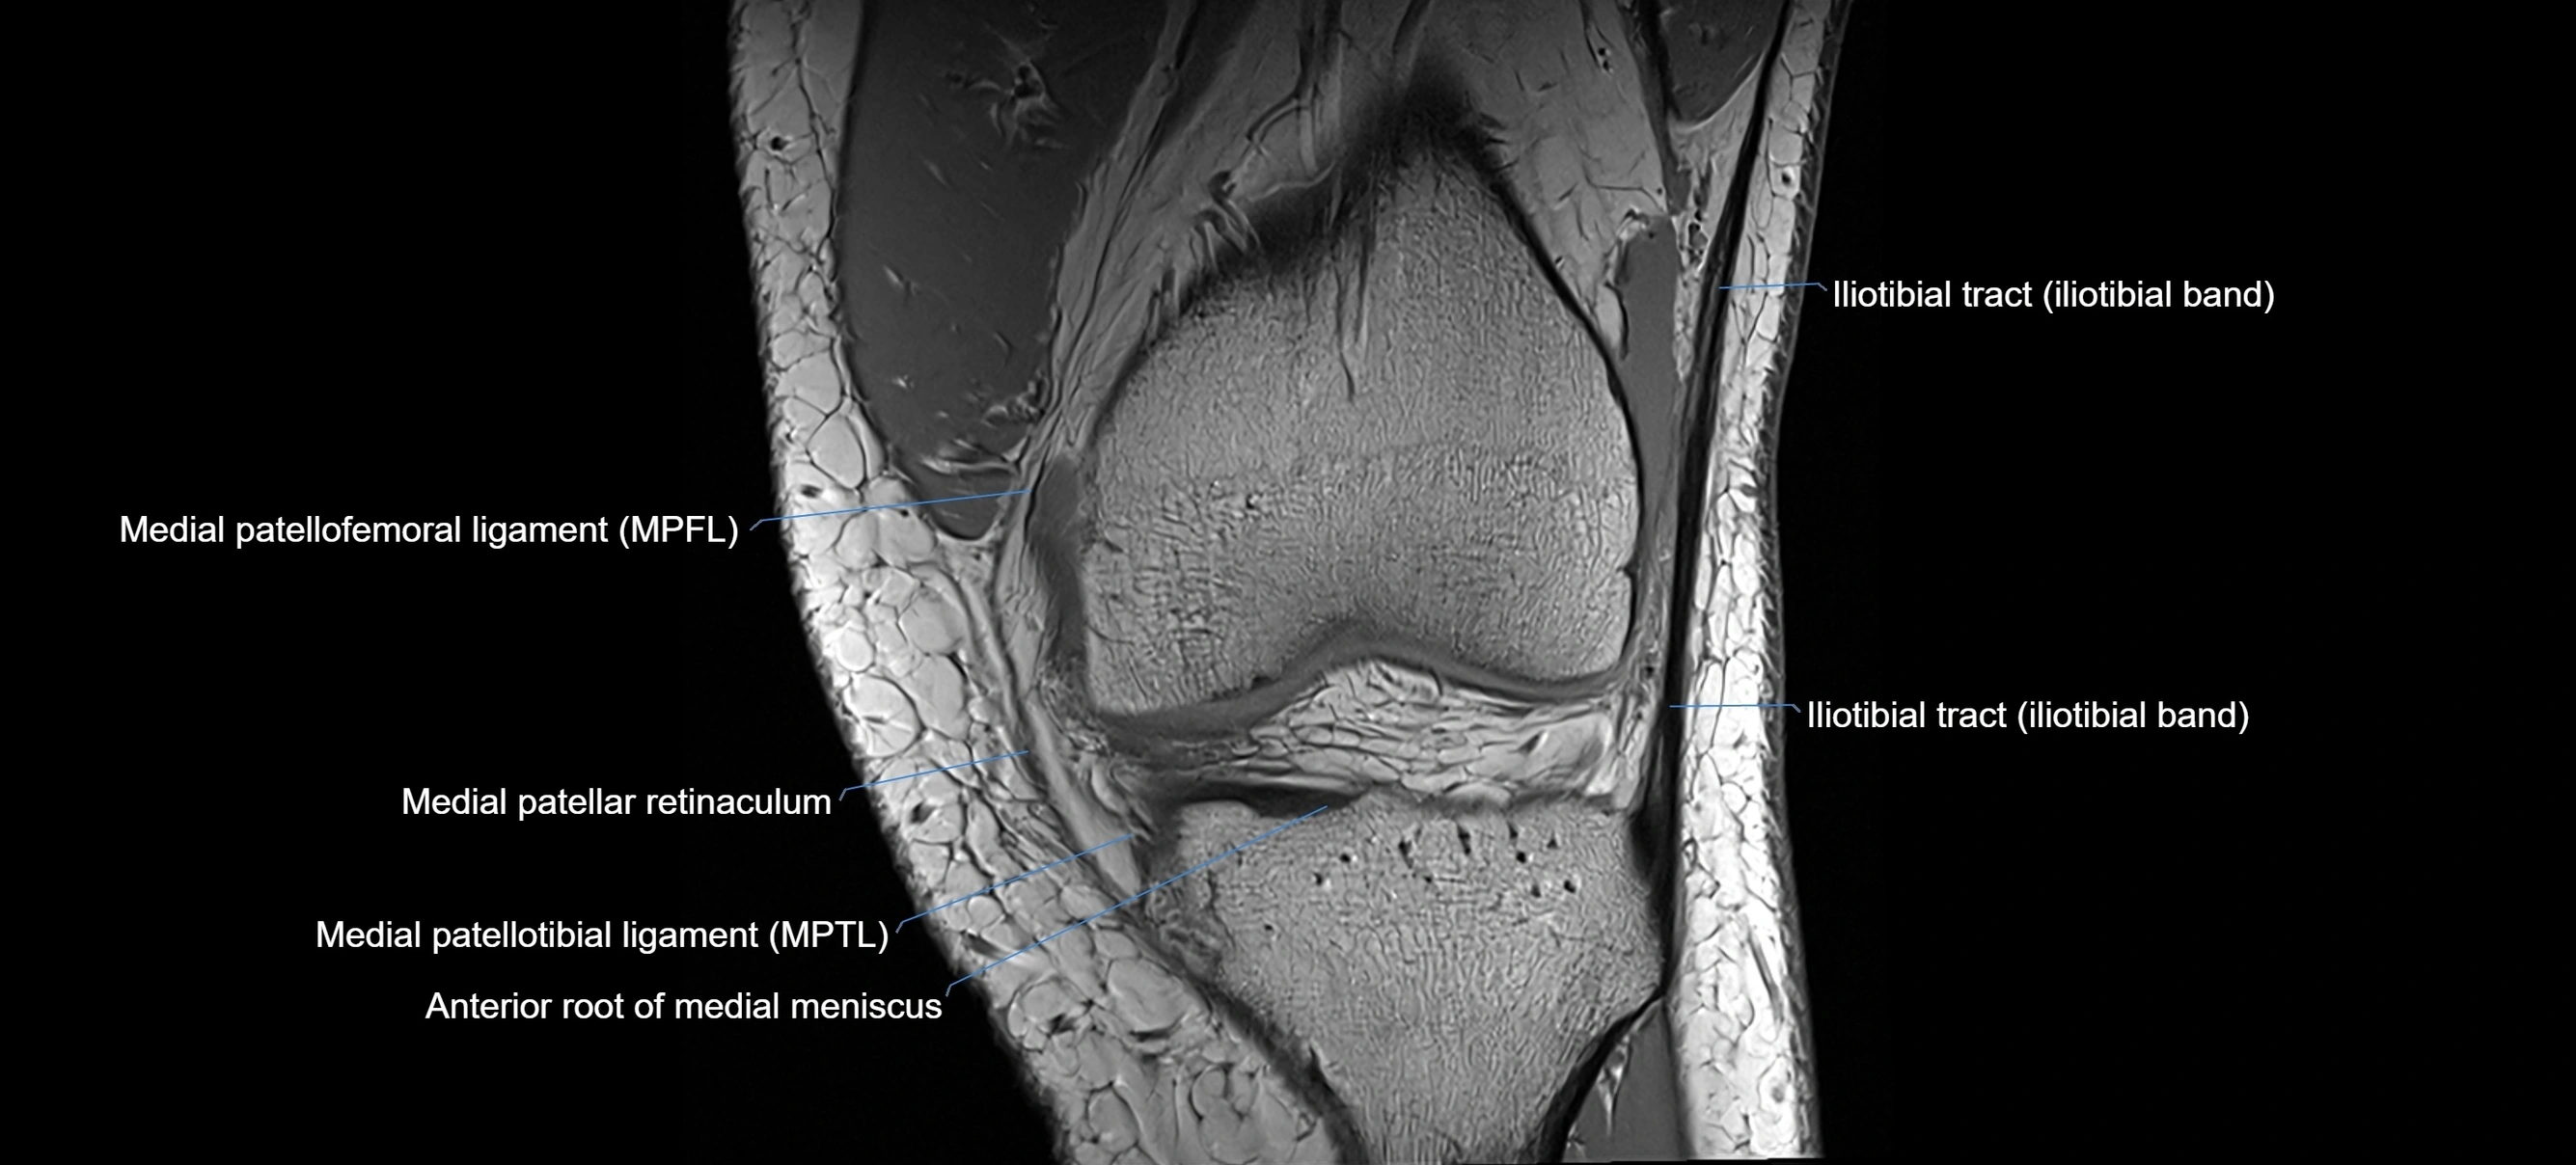

MRI images

image